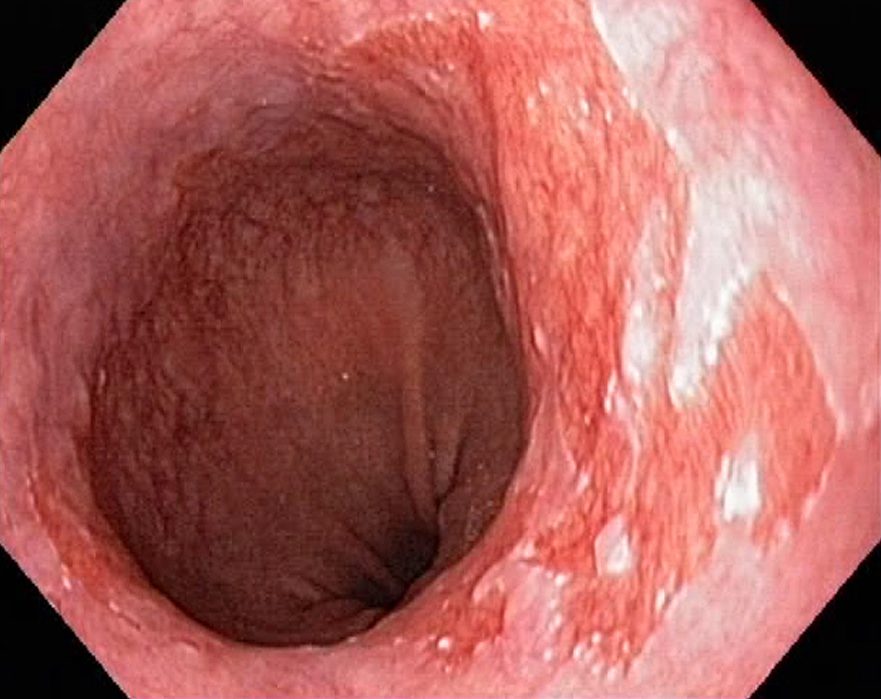

Barrets Oesophagus (NBI, Narrow Band Imaging)